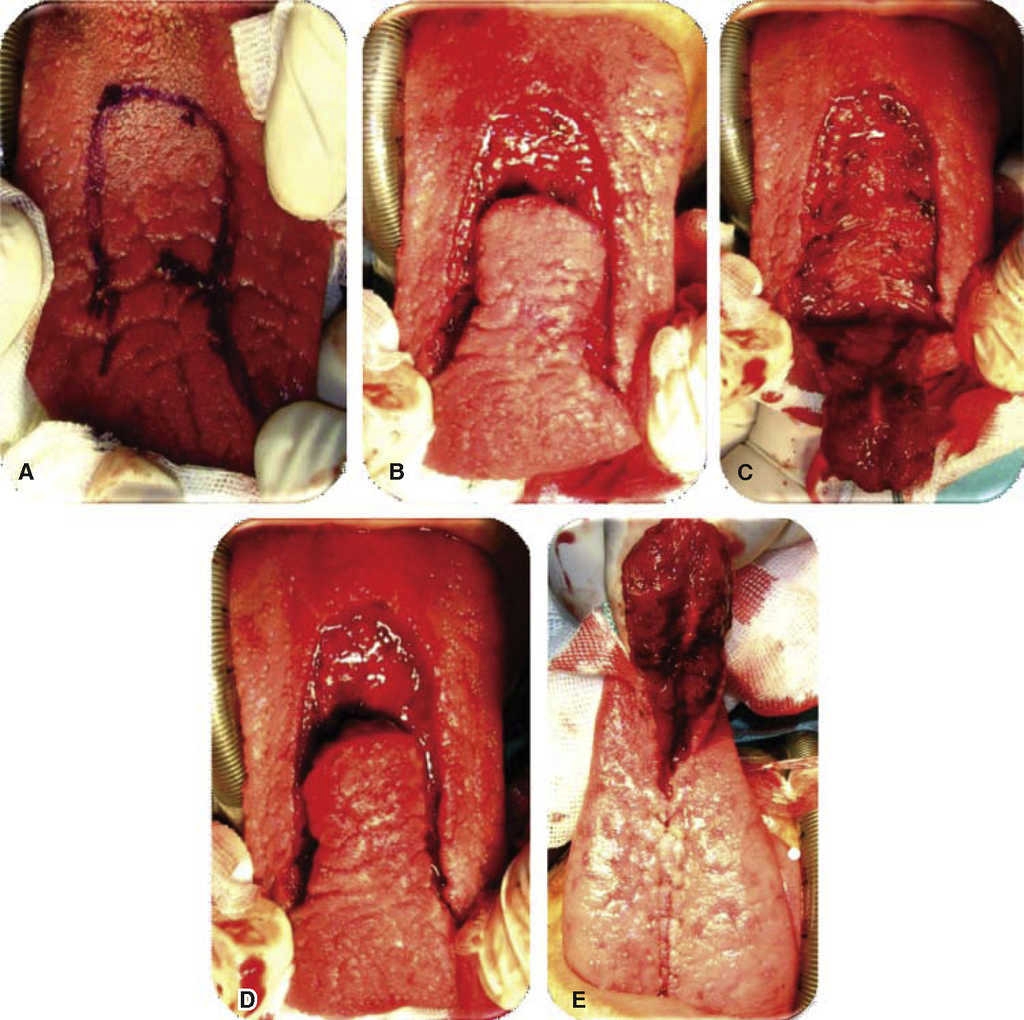

Evolution. Weekly controls were conducted at 7, 14, 21 and 28 days after surgery. At controls executed at 7, 14 and 21 days, excellent evolution was observed: with well-hydrated mucosa of suitable color, surgical wounds free of dehiscence, infection or compromised vascularity (Figures 5 and 6). Suitable tongue mobility was observed without phonation alterations. On day 21, under local anesthesia the tongue flap was separated with clamps, no accidents or complications were encountered. The patient was programmed for another visit seven days later, and was prescribed with amoxicillin, by mouth, 500 mg every eight hours and ibuprofen by mouth, every eight hours for five days. At the 28th day control, clean surgical wounds were observed without signs of dehiscence or infection, as well as 100% closed oro-nasal fistula, dorsum of the tongue without functional or esthetic alterations. The patient was discharged and programmed for a one month later control appointment.

Figure 6 Tongue flap clamping and removal. A. Surgical bed; removal of tongue flap. B. Surgical bed: donor site. C. 100% closure of palatal fistula. D. Donor site suture.